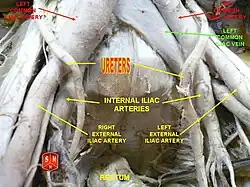

A number of structures pass by, above, and around the ureters on their path down from the kidneys to the bladder.[2] In its upper part, the ureter travels on the psoas major muscle and sits just behind the peritoneum. As it passes down the muscle, it travels over the genitofemoral nerve. The inferior vena cava and the abdominal aorta sit to the midline of the right and left ureters, respectively.[2] In the lower part of the abdomen, the right ureter sits behind the lower mesentery and the terminal ileum, and the left ureter sits behind the jejunum and the sigmoid colon.[2] As the ureters enter the pelvis, they are surrounded by connective tissue, and travel backward and outward, passing in front of the internal iliac arteries and internal iliac veins. They then travel inward and forward, crossing the umbilical, inferior vesical, and middle rectal arteries.[2] From here, in males, they cross under the vas deferens and in front of the seminal vesicles to enter the bladder near the trigone.[2] In females, the ureters pass behind the ovaries and then travel in the lower midline section of the broad ligament of the uterus. For a short part, the uterine arteries travel on top for a short (2.5 cm (1 in)) period. They then pass by the cervix, traveling inward towards the bladder.[2]

The arteries which supply the ureter vary along its course. The upper third of the ureter, closest to the kidney, is supplied by the renal arteries.[2] The middle part of the ureter is supplied by the common iliac arteries, direct branches from the abdominal aorta, and gonadal arteries;[1] the gonadal arteries being the testicular artery in men and the ovarian artery in women.[2] The lower third of the ureter, closest to the bladder, is supplied by branches from the internal iliac arteries, mainly the superior and inferior vesical arteries.[1] The arterial supply can be variable, with arteries that contribute include the middle rectal artery, branches directly from the aorta,[1] and, in women, the uterine and vaginal arteries.[2]

A kidney stone can move from the kidney and become lodged inside the ureter, which can block the flow of urine, as well as cause a sharp cramp in the back, side, or lower abdomen.[9] Pain often comes in waves lasting up to two hours, then subsides, called renal colic.[10] The affected kidney could then develop hydronephrosis, should a part of the kidney become swollen due to blocked flow of urine.[9] It is classically described that there are three sites in the ureter where a kidney stone will commonly become stuck: where the ureter meets the renal pelvis; where the iliac blood vessels cross the ureters; and where the ureters enter the urinary bladder,[9] however a retrospective case study, which is a primary source, of where stones lodged based on medical imaging did not show many stones at the place where the iliac blood vessels cross.[11]